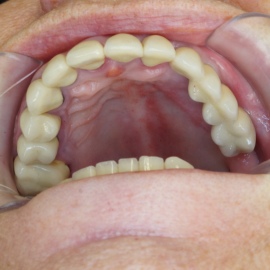

Bezzębie całkowite górne. Początkowo wykonane na mieście mosty całoceramiczne wydawały sie sukcesem, ale po roku pojawiły sie obrzęki i krwawienie z dziąseł. Pacjentka zgłosiła się do leczenia. Usunięto wszystkie zęby w szczęce. Sterowana regeneracja tkanek kości wyrostka, modelowanie kształtu i objętości tkanek miękkich, mosty porcelanowe przykręcane do implantów. Zadowalający wynik anatomiczny i estetyczny.